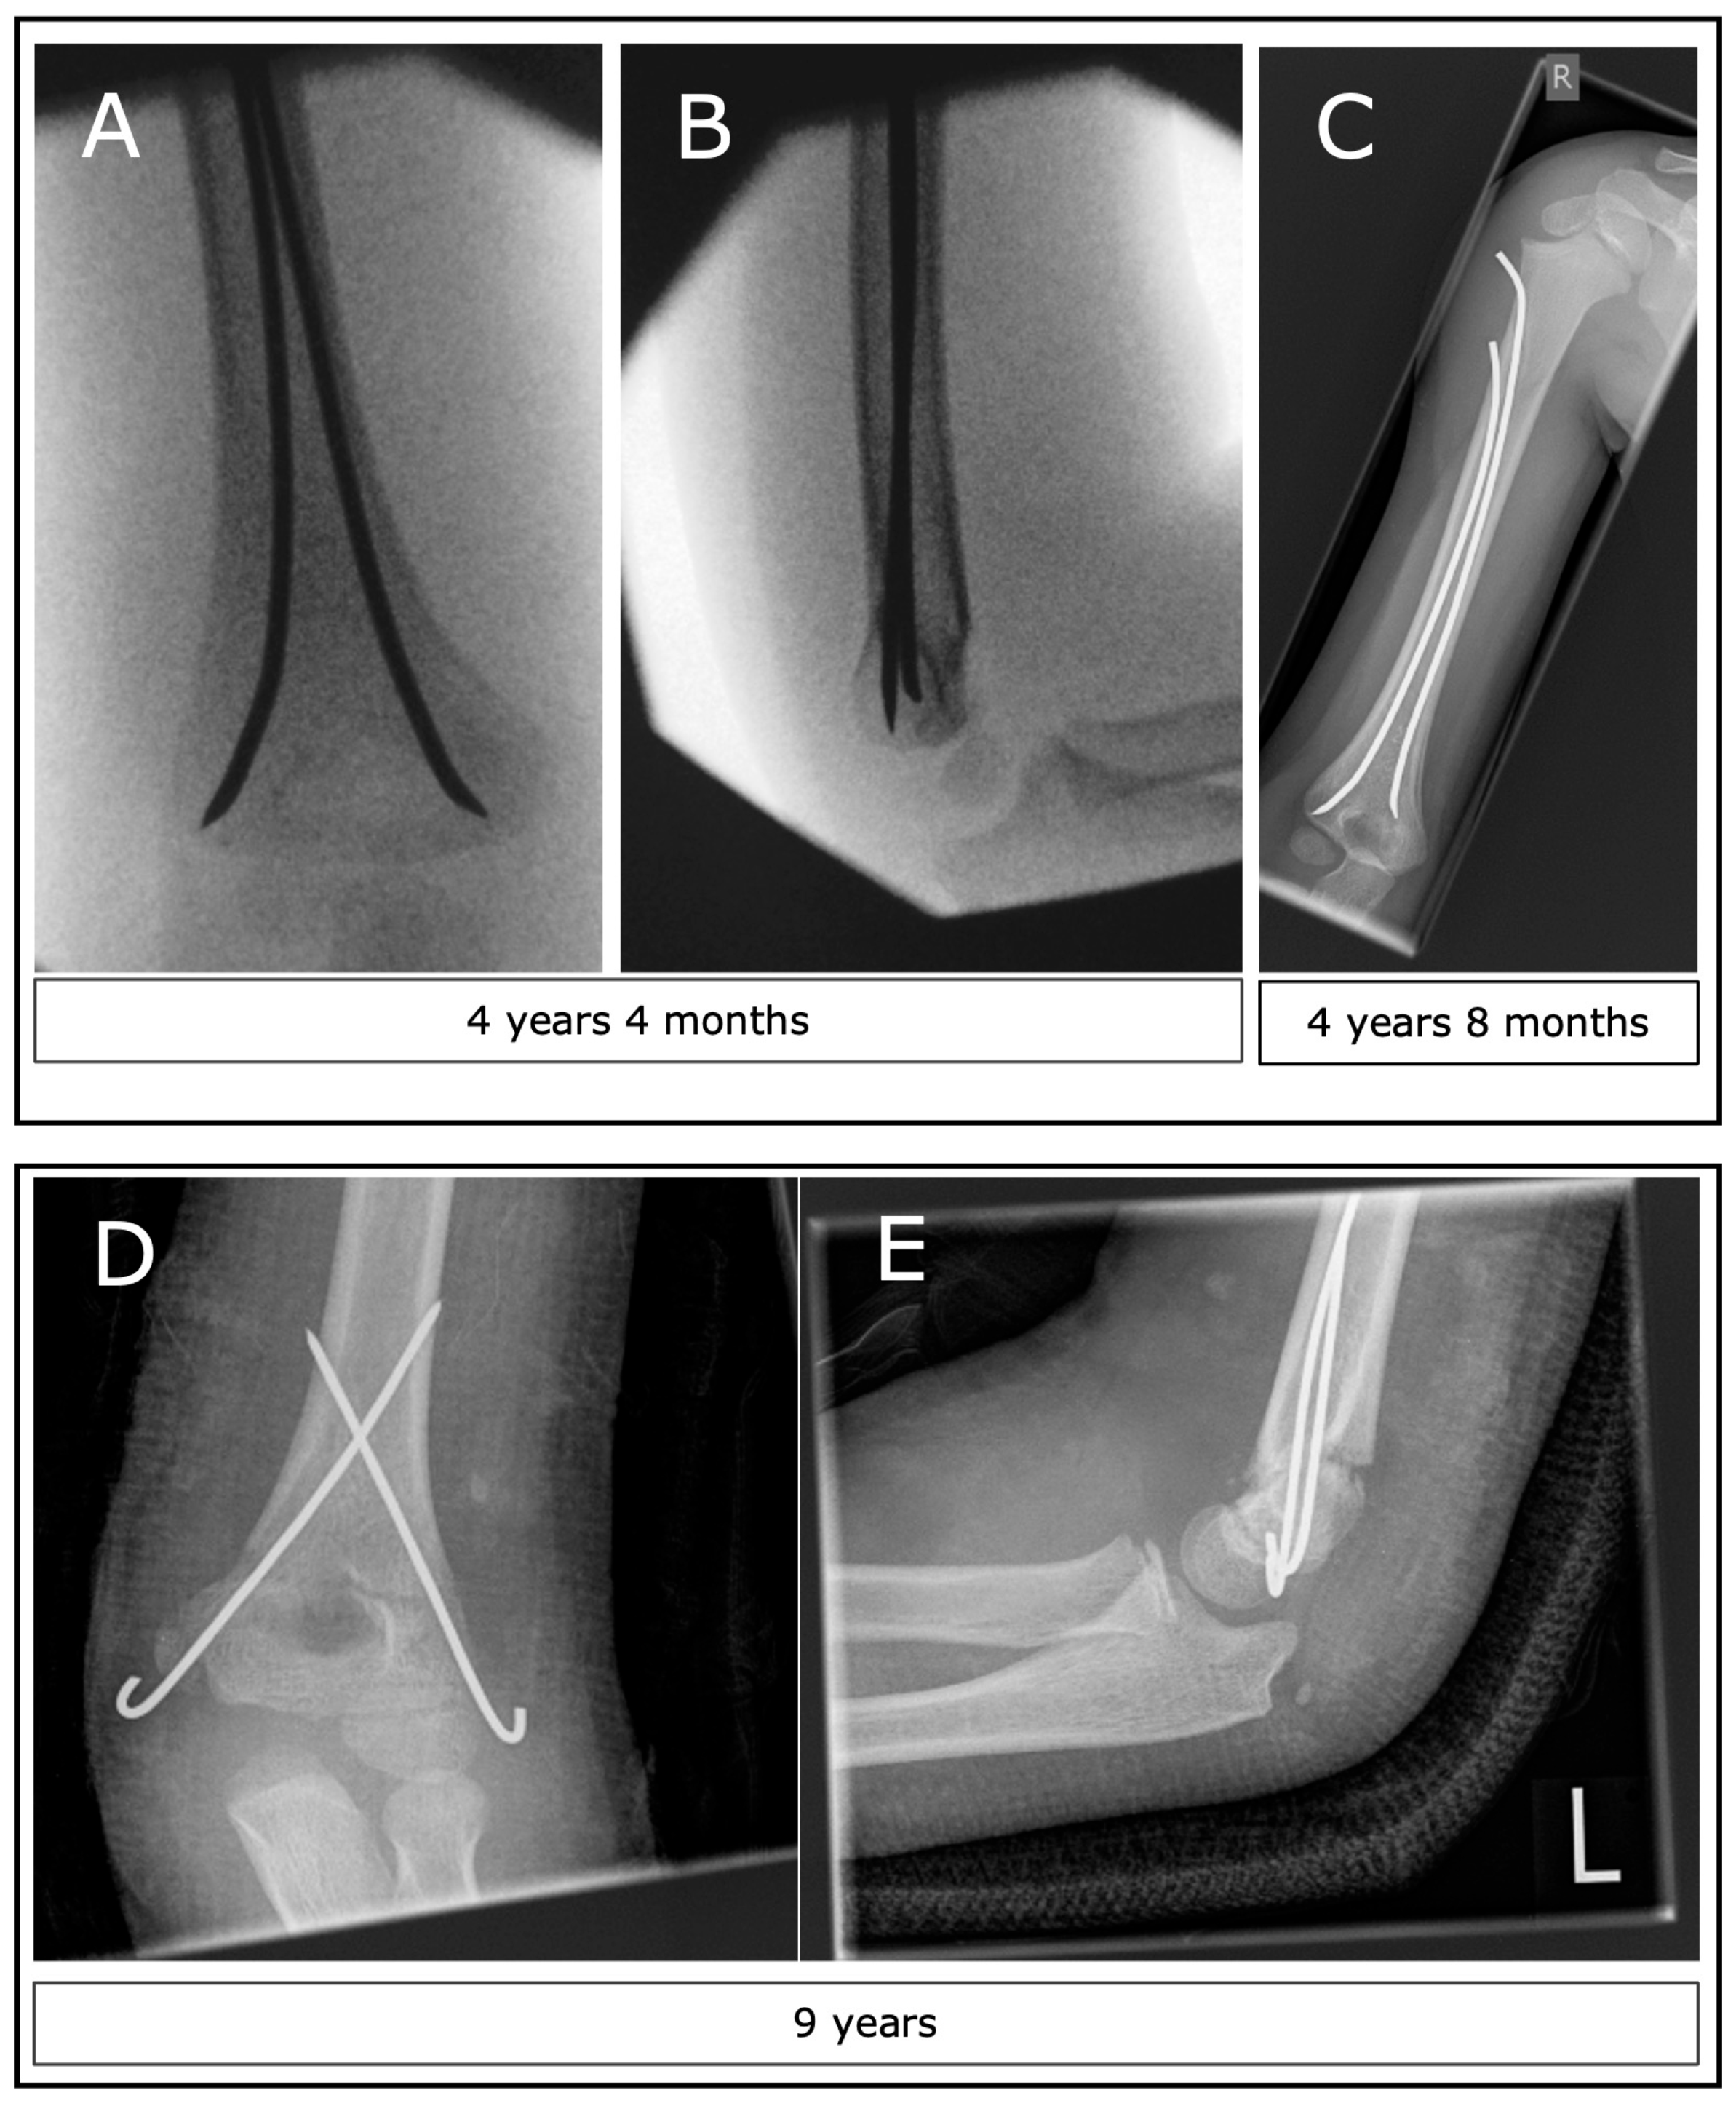

3.6. Operative Technique (CRK, ESIN, ORK)